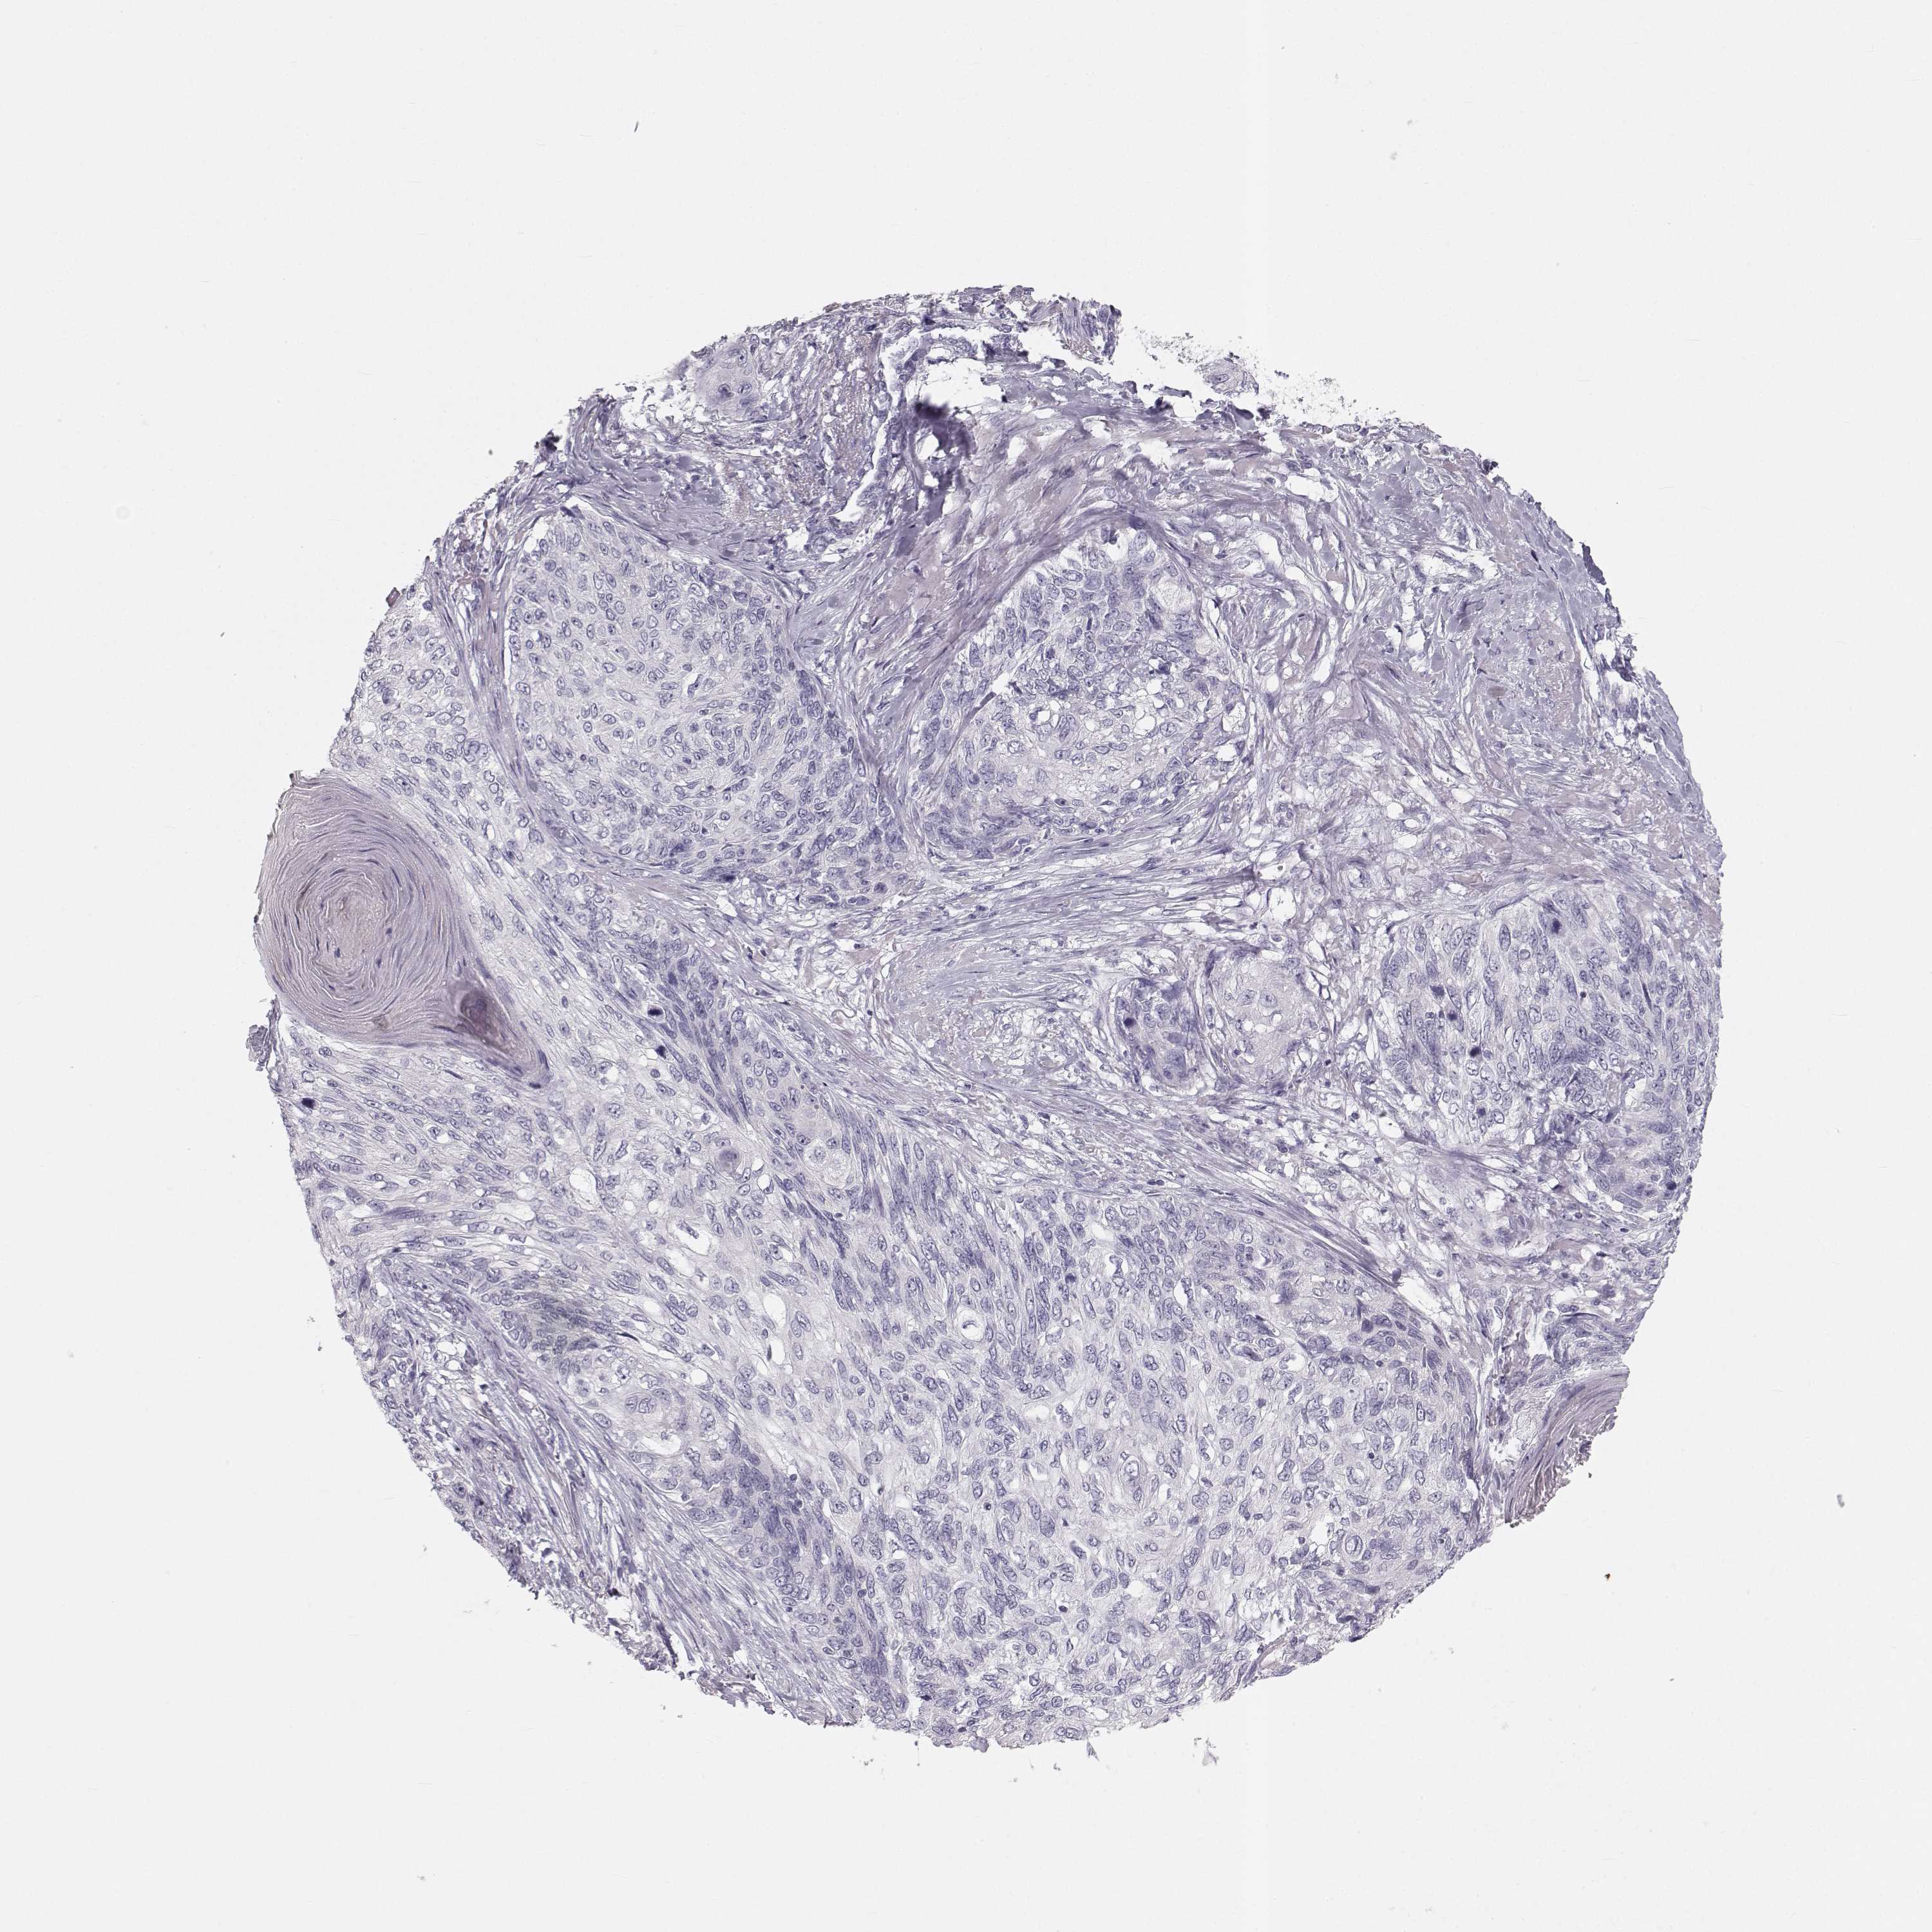

Basal cell and squamous cell cancer

SKIN CANCER - Protein expressioni

A mouse-over function shows sample information and annotation data. Click on an image to view it in a full screen mode. Samples can be filtered based on level of antibody staining by selecting one or several of the following categories: high, medium, low and not detected. The assay and annotation is described here.

Antibody stainingi

Antibody staining in the annotated cell types in the current human tissue is reported as not detected, low, medium, or high, based on conventional immunohistochemistry profiling in selected tissues. This score is based on the combination of the staining intensity and fraction of stained cells.

Each image is clickable and will lead to virtual microscopy that enables deeper exploration of all samples and also displays staining intensity scores, fraction scores and subcellular localization as well as patient and tissue information for each sample.

Antibody HPA052271

Antibody HPA059602

Staining

High

Medium

Low

Not detected

Intensity

Strong

Moderate

Weak

Negative

Quantity

>75%

75%-25%

<25%

None

Location

Nuclear

Cytoplasmic/membranous

Cytoplasmic/membranous,nuclear

Basal cell carcinoma

Squamous cell carcinoma, NOS